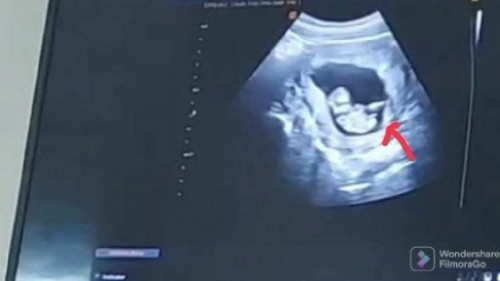

สวัสดีจ้าแม่ๆ ตอนนี้เราอายุครรภ์ 12สัปดาห์แล้ว วันนี้เราไปซาวด์มา หมอบอกนอนอ้าขาเลย แล้วมีติ่งเล็กๆแบบนี้ มีใครพอดูออกหรือมีประสบการณ์มั้ยคะ ว่าติ่งน้อยๆนี้ จะเป็น ช/ญ กันนะ (พอได้ลุ้นจ้า) #ท้องแรกคะ #ขอบคุณล่วงหน้านะคะ #ขอบคุณสำหรับคำตอบค่ะ